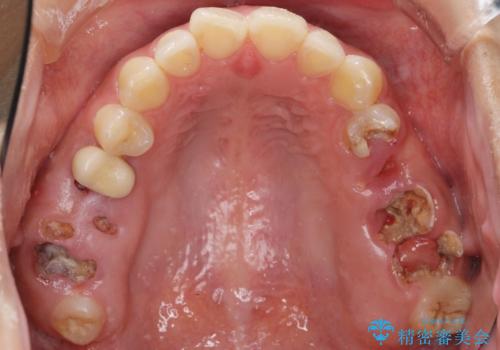

- う蝕により奥歯がボロボロで咬めないことを主訴に来院された患者様です。

奥歯2本(右上76)はう蝕が深く保存不可能な状態であったため、やむなく抜歯しました。

インプラントも入れ歯も抵抗があるとのご相談により、自家歯牙移植を提案しました。

使っていない親知らず(右上8)を右上7抜歯窩に移植し、支台歯としてブリッジによる補綴治療を行いました。